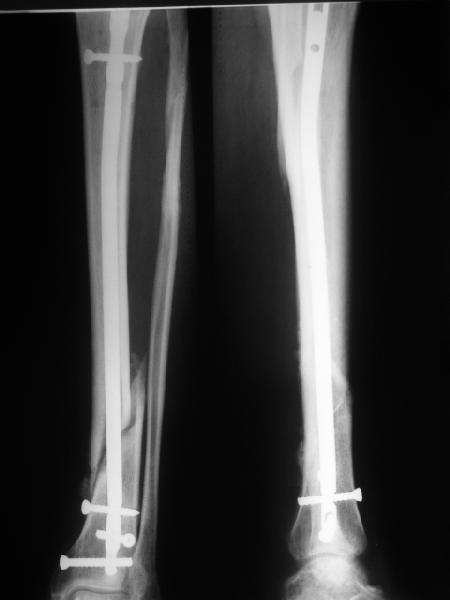

Re: неправильно фиксированный перелом

>СА> представленные снимки этому подтверждение-данный кососпиральный

СА> перелом репонируется идеально только открыто,что при БИОС не так существенно.

Здесь проблема не в идеальности репозиции, а в запасе усталостной прочности. Срастаться там может небыстро, диастазы довольно большие.

И когда еще и отломок короткий, и отверстие совсем рядом, это может привести к перелому стержня. За последние годы у нас было несколько пациентов, оперированных в других учреждениях с

подобным положением отломков, с такими переломами гвздей. И сейчас переделать куда как проще и легче, чем иметь дело со сломанным гвоздем.

Антон, дорогой, важнее вальгуса тут близость верхнего отверстия к перелому и отсутствие уверенности в быстром сращении из-за большого

диастаза.

В Кемпбелле можно прочитать, что Fractures in the distal third of the tibia had the highest frequency of nail breakage.

Вообще, этот вопрос обсуждался давно, и еще в статье R. Bucholz (1987) про переломы гвоздей указывалось, что расстояние от ближайшего отверстия до перелома должно быть не менее 5 см, иначе есть угроза усталостного перелома. По литературе переломы гвоздей в нижней трети

tibia достигают 4,3%.